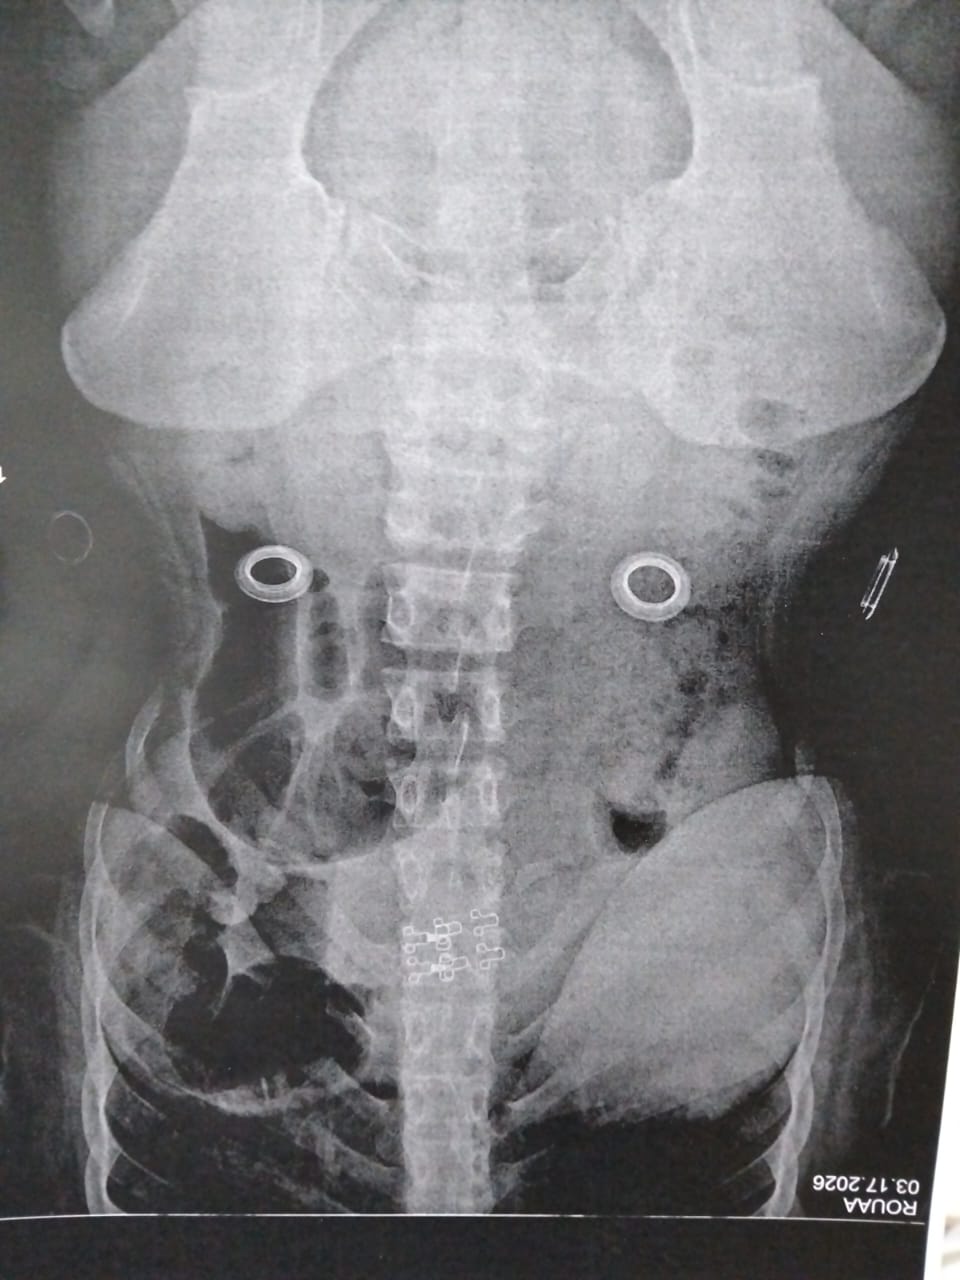

امساك وترجيع دم

اعاني من امساك شديد مع خروج دم مع البراز والم اثناء وبعد البراز في فتحة الشرج وانت متزوجة منذ شهرين...